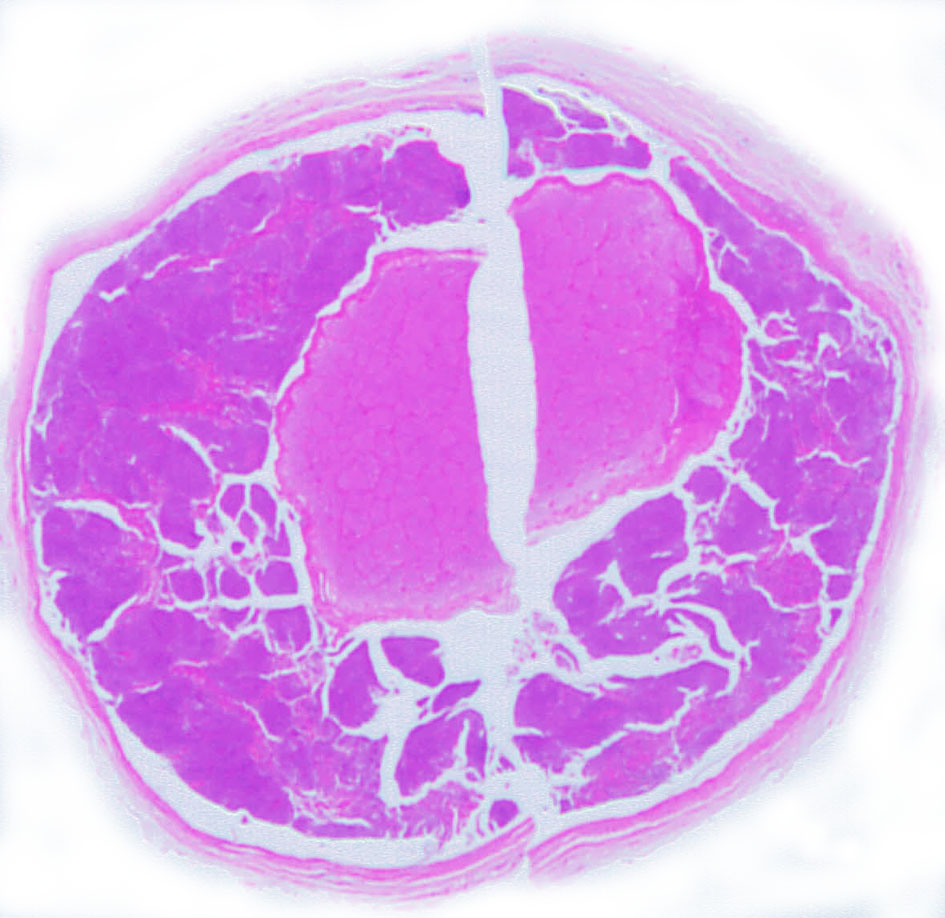

左側は,摘出標本の輪切りの写真です。この部位は腫瘍の発生した部位ではありません。一番外側にみえるのは視神経鞘 optic sheathという膜です。その内側が髄膜腫で,その内側が視神経です。すなわち髄膜腫は,視神経鞘と視神経の間のくも膜下腔を,這うように伝わって増殖伸展しています。このくも膜下腔には視神経への栄養動脈や網膜動脈も入っているので,この腫瘍だけを視神経や細動脈を傷つけずに摘出することはできないのです。